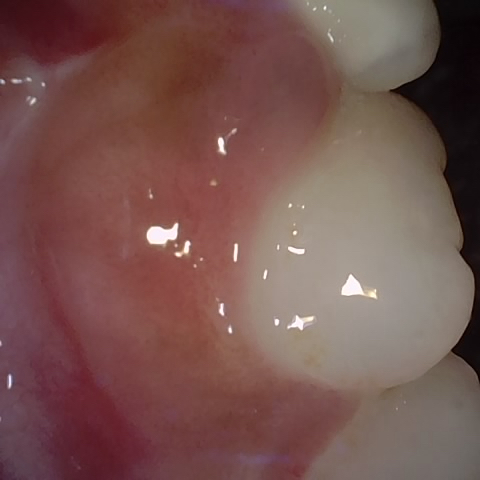

Image 903 / 1103

NHD39174

Annotated as "Good"

Original Image Rendering Image